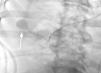

Mujer de 75 años, exfumadora, que ingresa en UCI por insuficiencia respiratoria secundaria a Neumonía. Presenta evolución tórpida, con desarrollo de Síndrome de Distrés Respiratorio Agudo y necesidad de ventilación mecánica prolongada. El destete se ve dificultado por la aparición de derrame pleural (DP) bilateral, por lo que se coloca un drenaje pleural ecoguiado (Pleurocath® 12 French). A los 30 minutos presenta cuadro de hipotensión severa, sudoración y palidez. Tras estabilización inicial se solicita TAC torácico, que objetiva hemotórax derecho y una imagen redondeada que sugiere pseudoaneurisma de circulación pulmonar periférica (fig. 1). Se contacta con Radiología Intervencionista y se decide realizar angiografía pulmonar, confirmando la existencia de un pseudoaneurisma arterial procedente de una rama de la lobar descendente derecha (fig. 2). Se emboliza con coils (fig. 3), presentando buena evolución y siendo dada de alta a planta sin incidencias.